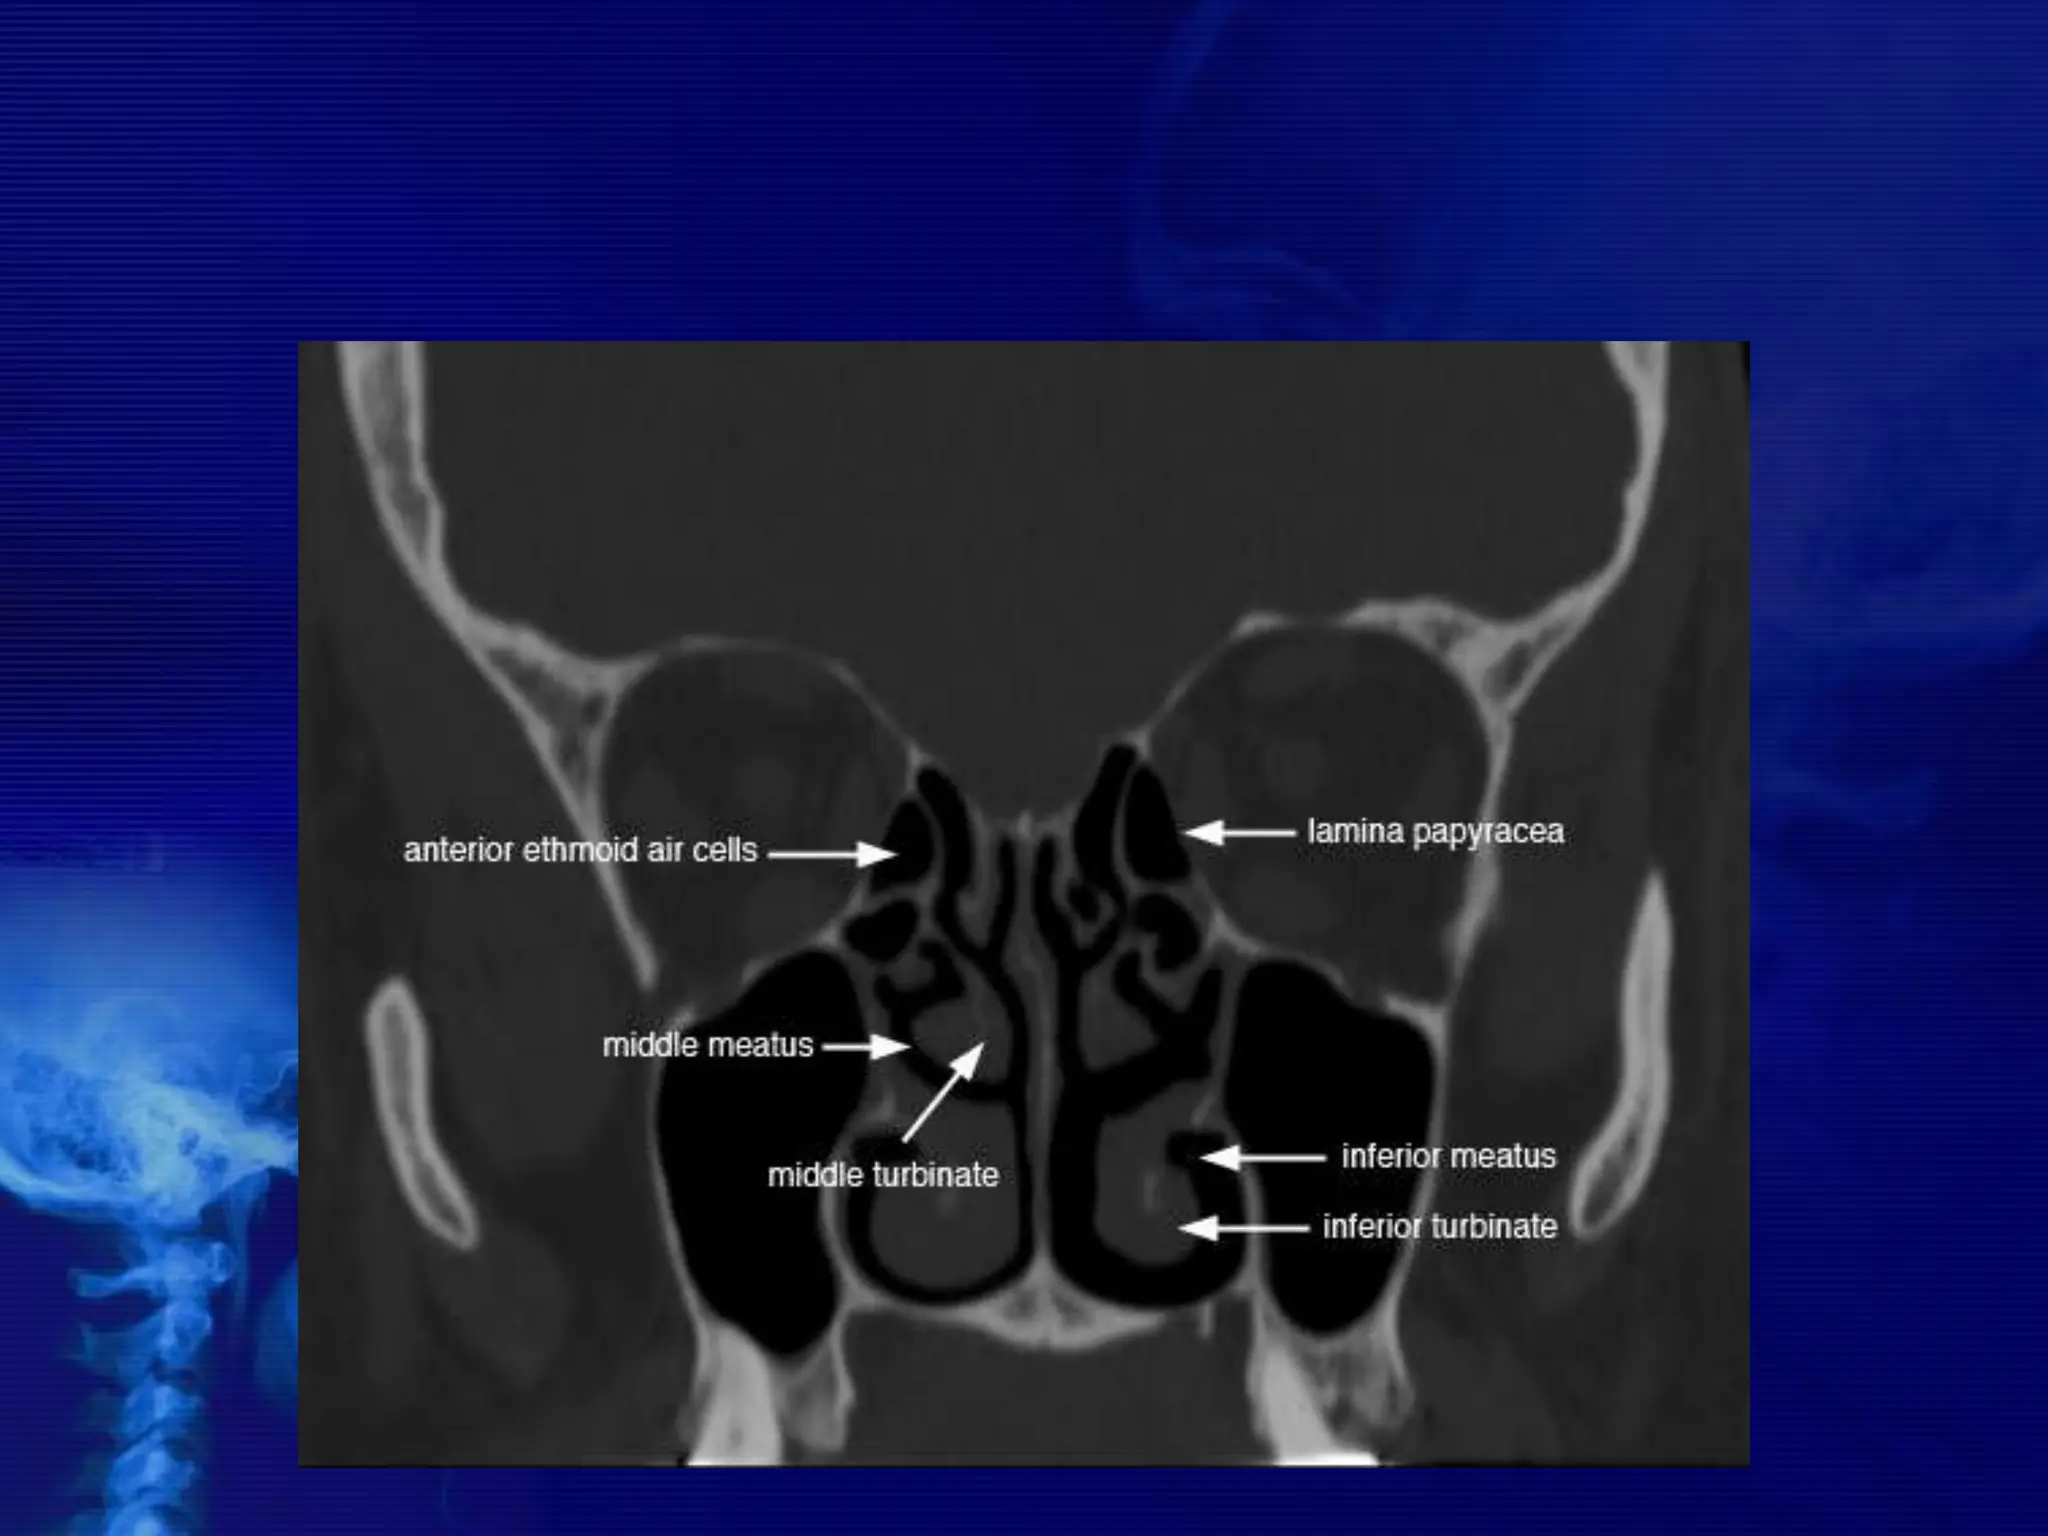

Osteomeatal unit

• The osteomeatal unit (OMU) includes the (1) maxillary

sinus ostium, (2) ethmoid infundibulum, (3) anterior

ethmoid air cells, and (4) frontal recess.

The Lateral Wall of Nasal Cavity

Marked by 3

projections:

• Superior concha

• Middle concha

• Inferior concha

• The space below

each concha is

called a meatus.

1. Inferior meatus:

nasolacrimal duct

2. Middle meatus:

• Maxillary sinus

• Frontal sinus

• Anterior ethmoid

sinuses

3. Superior meatus:

posterior ethmoid

4. Sphenoethmoidal

recess: sphenoid

sinus

CROSS SECTIONAL ANATOMY –

AXIALS

CORONAL ANATOMY